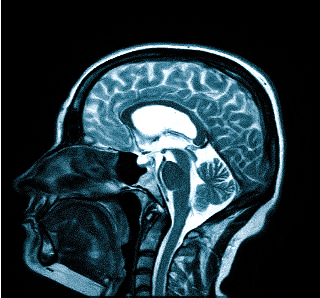

Для процедуры пациент ложится на стол-транспортер, который заезжает в томограф — сканирующее устройство. На время обследования пациент остается в трубе и должен сохранять неподвижность для получения четкого изображения. Процедура занимает от 15 минут.

Специальной подготовки не требуется, но необходимо предупредить врача о клаустрофобии, так как это может быть противопоказанием. Если во время МРТ вы почувствуете недомогание, сообщите об этом специалисту, проводящему обследование МРТ головы.

- МРТ (магнитно-резонансная томография) — процедура, которая предоставляет полное представление о состоянии исследуемой области и позволяет выявить заболевания. Четкие снимки получаются благодаря воздействию магнитного поля на организм.